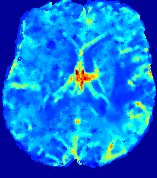

4.3.2 Diffusion Imaging via Advection-Diffusion

Slice #1Slice #2Slice #3Slice #4Slice #5Slice #6Dgtsuperscript𝐷gtD^{\text{gt}}Refer to captionRefer to captionRefer to captionRefer to captionRefer to captionRefer to captionDestsuperscript𝐷estD^{\text{est}}Refer to captionRefer to captionRefer to captionRefer to captionRefer to captionRefer to captionRefer to caption0.300.300.300.240.240.240.180.180.180.120.120.120.060.060.060.000.000.00(mm2/s)𝑚superscript𝑚2𝑠(mm^{2}/s)𝐕est𝟐subscriptnormsuperscript𝐕est2\|\bf{V}^{\text{est}}\|_{2}Refer to captionRefer to captionRefer to captionRefer to captionRefer to captionRefer to captionRefer to caption0.00300.00300.00300.00240.00240.00240.00180.00180.00180.00120.00120.00120.00060.00060.00060.00000.00000.0000(mm/s)𝑚𝑚𝑠(mm/s)

Figure 15: PIANO identifiability testing: diffusion imaging via advection-diffusion. Top row shows Dgtsuperscript𝐷gtD^{\text{gt}} used for simulating ground truth pure diffusion. Rows below show the estimated Destsuperscript𝐷estD^{\text{est}} and 𝐕est2subscriptnormsuperscript𝐕est2\|{\bf{V}}^{\text{est}}\|_{2} on corresponding slices. Note that the plotted value scale for 𝐕est2subscriptnormsuperscript𝐕est2\|{\bf{V}}^{\text{est}}\|_{2} is 0.01 of that for Dgtsuperscript𝐷gtD^{\text{gt}} and Destsuperscript𝐷estD^{\text{est}}.

Similarly, we test the behavior of PIANO when estimating both advection and diffusion from a pure diffusion-driven process. The goal is to determine if PIANO is able to recognize that there is only diffusion governing the given concentration time-series. We use the same ‘Diffusion Imaging’ data simulation of Sec. 4.2.1 as the concentration dataset, PIANO estimates both velocity 𝐕estsuperscript𝐕est{\bf{V}}^{\text{est}} and diffusivity Destsuperscript𝐷estD^{\text{est}}. Estimation results in Fig. 15 confirm PIANO’s identifiability again: the estimated 𝐕est2subscriptnormsuperscript𝐕est2\|{\bf{V}}^{\text{est}}\|_{2} is almost invisible compared to Destsuperscript𝐷estD^{\text{est}}, even plotted with a 1%percent11\% value range compared to that for Destsuperscript𝐷estD^{\text{est}}. On the other hand, Destsuperscript𝐷estD^{\text{est}} achieves comparable estimation performance as ‘Diffusion Imaging via Diffusion’ in which PIANO predicts Destsuperscript𝐷estD^{\text{est}} alone (shown in Fig. 13).